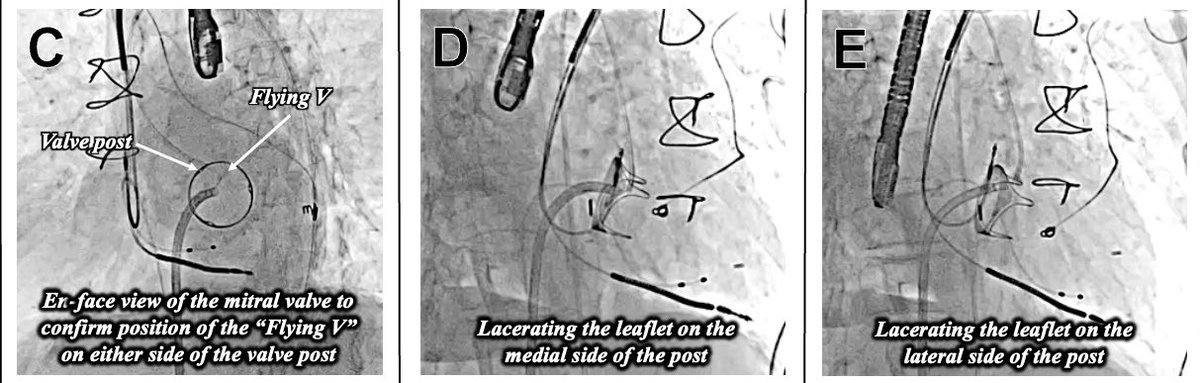

Presented today at #TCT2025 with simultaneous publication in @JACCJournals #JACCCI The first report of a βDouble LAMPOONβ procedure to mitigate the risk of LVOT obstruction after TMVR inside a βrotatedβ surgical valve, with a surgical valve post in the center of the LVOT, making